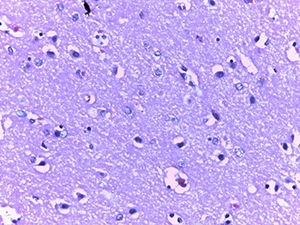

Микроскопическое исследование при окраске гематоксилином и эозином показало характерные изменения ядерного хроматина в эндотелиальных клетках сосудов микроциркуляторного русла (МЦР) головного мозга и в меньшей степени в периваскулярных астроцитах и ганглиозных клетках (см. рис. 1).

Так, имел место очаговый лизис хроматина с формированием небольшой внутриядерной вакуоли и распылением остатков хроматина ближе к внутреннему листку ядерной мембраны.

В ряде случаев описанная вакуоль содержала гиперхромную базофильную частицу по типу внутриядерного включения. Отмечалась тенденция к увеличению размеров данных вакуолей, которые в последующем занимали большую часть ядра и в конечном итоге приводили к полному нуклеолизу. Контуры клеток в виде остатков цитоплазмы сохранялись какое-то время.

Данные изменения ядерного хроматина имели место в сосудах МЦР всех отделов головного мозга, но более заметными были в коре больших полушарий и сером веществе подкорковых ядер.